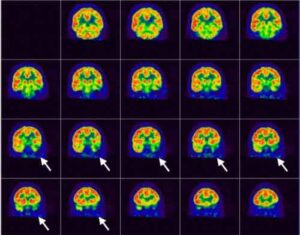

Roma, 23 set - L'epilessia e' il sintomo piu' comune nei pazienti con tumori cerebrali e l'approccio alla persona con...